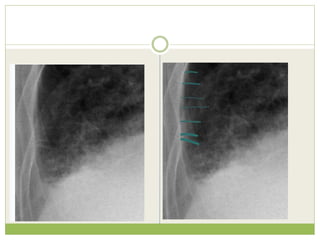

๏‚— The key findings of cardiogenic pulmonary edema

Kerley B lines (septal lines)

๏‚ก Seen at the lung bases, usually no more than 1 mm thick and 1 cm

long, perpendicular to the pleural surface

๏‚— Pleural effusions

๏‚ก Usually bilateral, frequently the right side being larger than the left

๏‚ก If unilateral, more often on the right

๏‚— Fluid in the fissures

๏‚ก Thickening of the major or minor fissure

๏‚— Peribronchial cuffing

๏‚ก Visualization of small doughnut-shaped rings representing fluid in

thickened bronchial walls